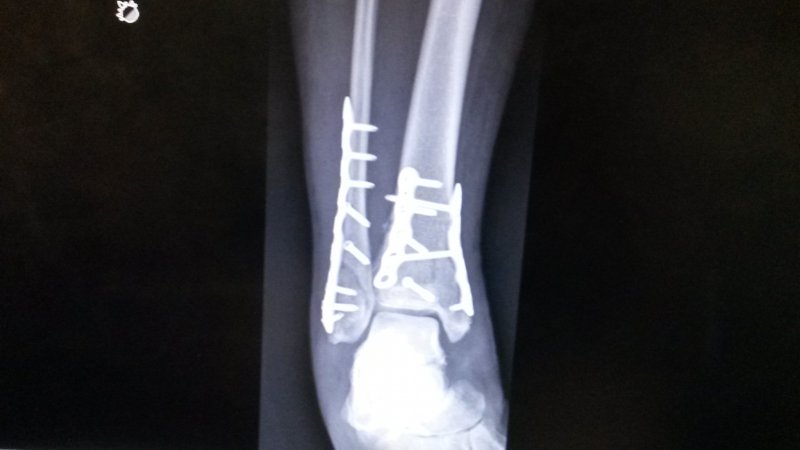

I broke my wife. 🙁

3 weeks ago we crashed our tandem bike. It was 1/4 mile from our house at the end of our ride.

It took 3 plates and 16 screws to put Helen's ankle back together.

She looks forward to getting back on a bike in 8-10 weeks.